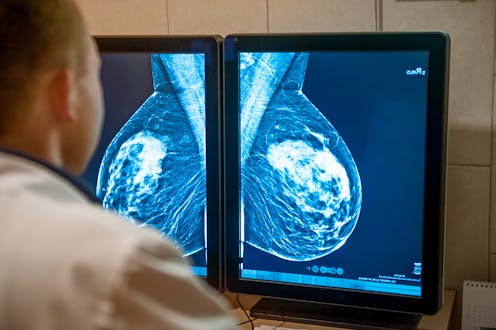

In recent years, scientists have developed AI algorithms that can analyse mammograms for signs of breast cancer. These algorithms may be as good as or better at finding cancers than human radiologists, and save the health-care system money.

In Australia, as in many countries around the world, two specially trained health professionals, usually radiologists, review each screening mammogram for signs of cancer. If the two radiologists disagree, a third is consulted.

AI has been investigated to support radiologists, replace a radiologist, or as a triage tool to identify the mammograms at highest risk so these can be reviewed by a radiologist. However, there’s no consensus yet as to how to best implement AI in breast cancer screening.